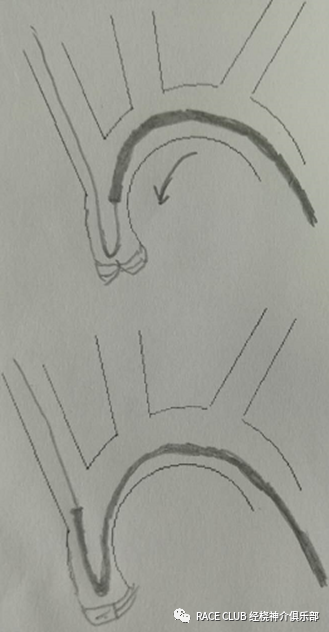

特殊情况进管( Ⅲ型弓)

用西蒙2导管

造影导丝是什么全脑血管造影术_https://www.jmylbn.com_新闻资讯_第15张

特殊情况进管(共干)

造影导丝是什么全脑血管造影术_https://www.jmylbn.com_新闻资讯_第16张

1.悬停技术

2.西蒙2导管

3.其它导管,如MANI管

造影导丝是什么全脑血管造影术_https://www.jmylbn.com_新闻资讯_第17张

造影导丝是什么全脑血管造影术_https://www.jmylbn.com_新闻资讯_第18张

造影导丝是什么全脑血管造影术_https://www.jmylbn.com_新闻资讯_第19张

西蒙2导管的塑形(一)

造影导丝是什么全脑血管造影术_https://www.jmylbn.com_新闻资讯_第20张

•左锁骨下动脉塑形:

导丝带西蒙导管过弓,回撤导丝到大弯后,回撤导管,让导管头端进左锁骨下动脉,进导丝,走远,跟进导管,当大弯顶端快到左锁骨下动脉开口时,撤导丝,顶导管,可塑形成功。

注意:

1.导丝要走远,不然导管跟不上。

2.导管大弯不能进左锁骨下

难点:

左锁骨下动脉开口不好找,也可以从左颈总动脉塑形

西蒙导管的塑形(二)

造影导丝是什么全脑血管造影术_https://www.jmylbn.com_新闻资讯_第21张

•升主动脉塑形:用导丝将西蒙导管导入升主动脉深部,撤导丝,边进导管,边旋转,塑成横“8”字形,进导丝,解旋,塑形成功。

西蒙导管的塑形(三)

造影导丝是什么全脑血管造影术_https://www.jmylbn.com_新闻资讯_第22张

• 降主动脉塑形:

导丝将导管导入大弯顶点大约和弓顶点重合,撤导丝,顺(逆)时针旋转,使弯曲部分缠绕,顶导管过弓顶点,边顶边反方向旋转,解旋(也可以后撤,先解旋塑形,再顶导管)

注意点:

1.不能暴力,试3次不行,换个方法

2.要记住塑形时的旋转方向,解旋方向与之相反,这种方法很容易拧折导管

1.不易缠绕

2.如果左锁骨下动脉开口正好在弓顶点,或超3型弓,导管可能会定在锁骨下动脉开口或弓顶部,很难到升主动脉

西蒙导管的塑形(四)

造影导丝是什么全脑血管造影术_https://www.jmylbn.com_新闻资讯_第23张

•主动脉瓣塑形:

进导丝,利用主动脉,导丝返折向上走,将导丝送入右颈总动脉或右锁骨下动脉,跟进导管,让导管大弯过主动脉瓣,撤导丝,塑形成功

1.进导丝要十分小心,要导丝头端位置和方向,尽量别进左心室,否则会出现室性心律失常

2.有损伤主动脉瓣和掉斑块的风险

3.不到万不得已,别用这种方法,有器质性心脏病的禁用